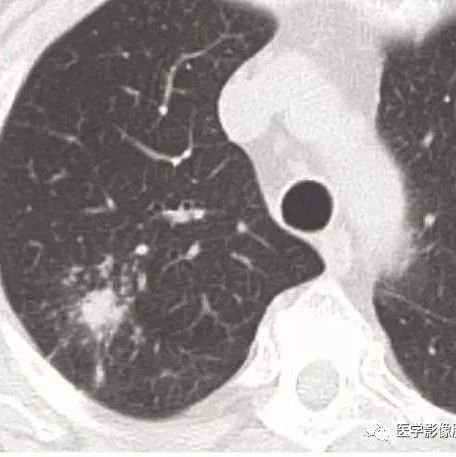

来源:听李医生说 42岁女性患者,因为发热、咳嗽10天收入院,住呼吸内科。这是一个特殊的患者,因为她是医院饭堂一名职工,据说还有点职位的。也是某院领导的亲戚。领导已经跟科主任说了,兄弟,关照一下。不就是一个发热、咳嗽的患者嘛,没啥,估计也就一个普通肺炎,用几天抗生素就好了。主任跟管床医生说,但是沟通过程尽量要小心,别出岔子了,听说这女的脾气还挺犟。42岁,年纪不大,但也不小,入院时胸片已经提示左肺炎了,再加上抽血化验了感染指标都是偏高的,管床医生用听诊器仔细听了双肺,左肺的确有湿罗音。所以诊断肺炎那是板上钉钉的事情,不会错的了。...